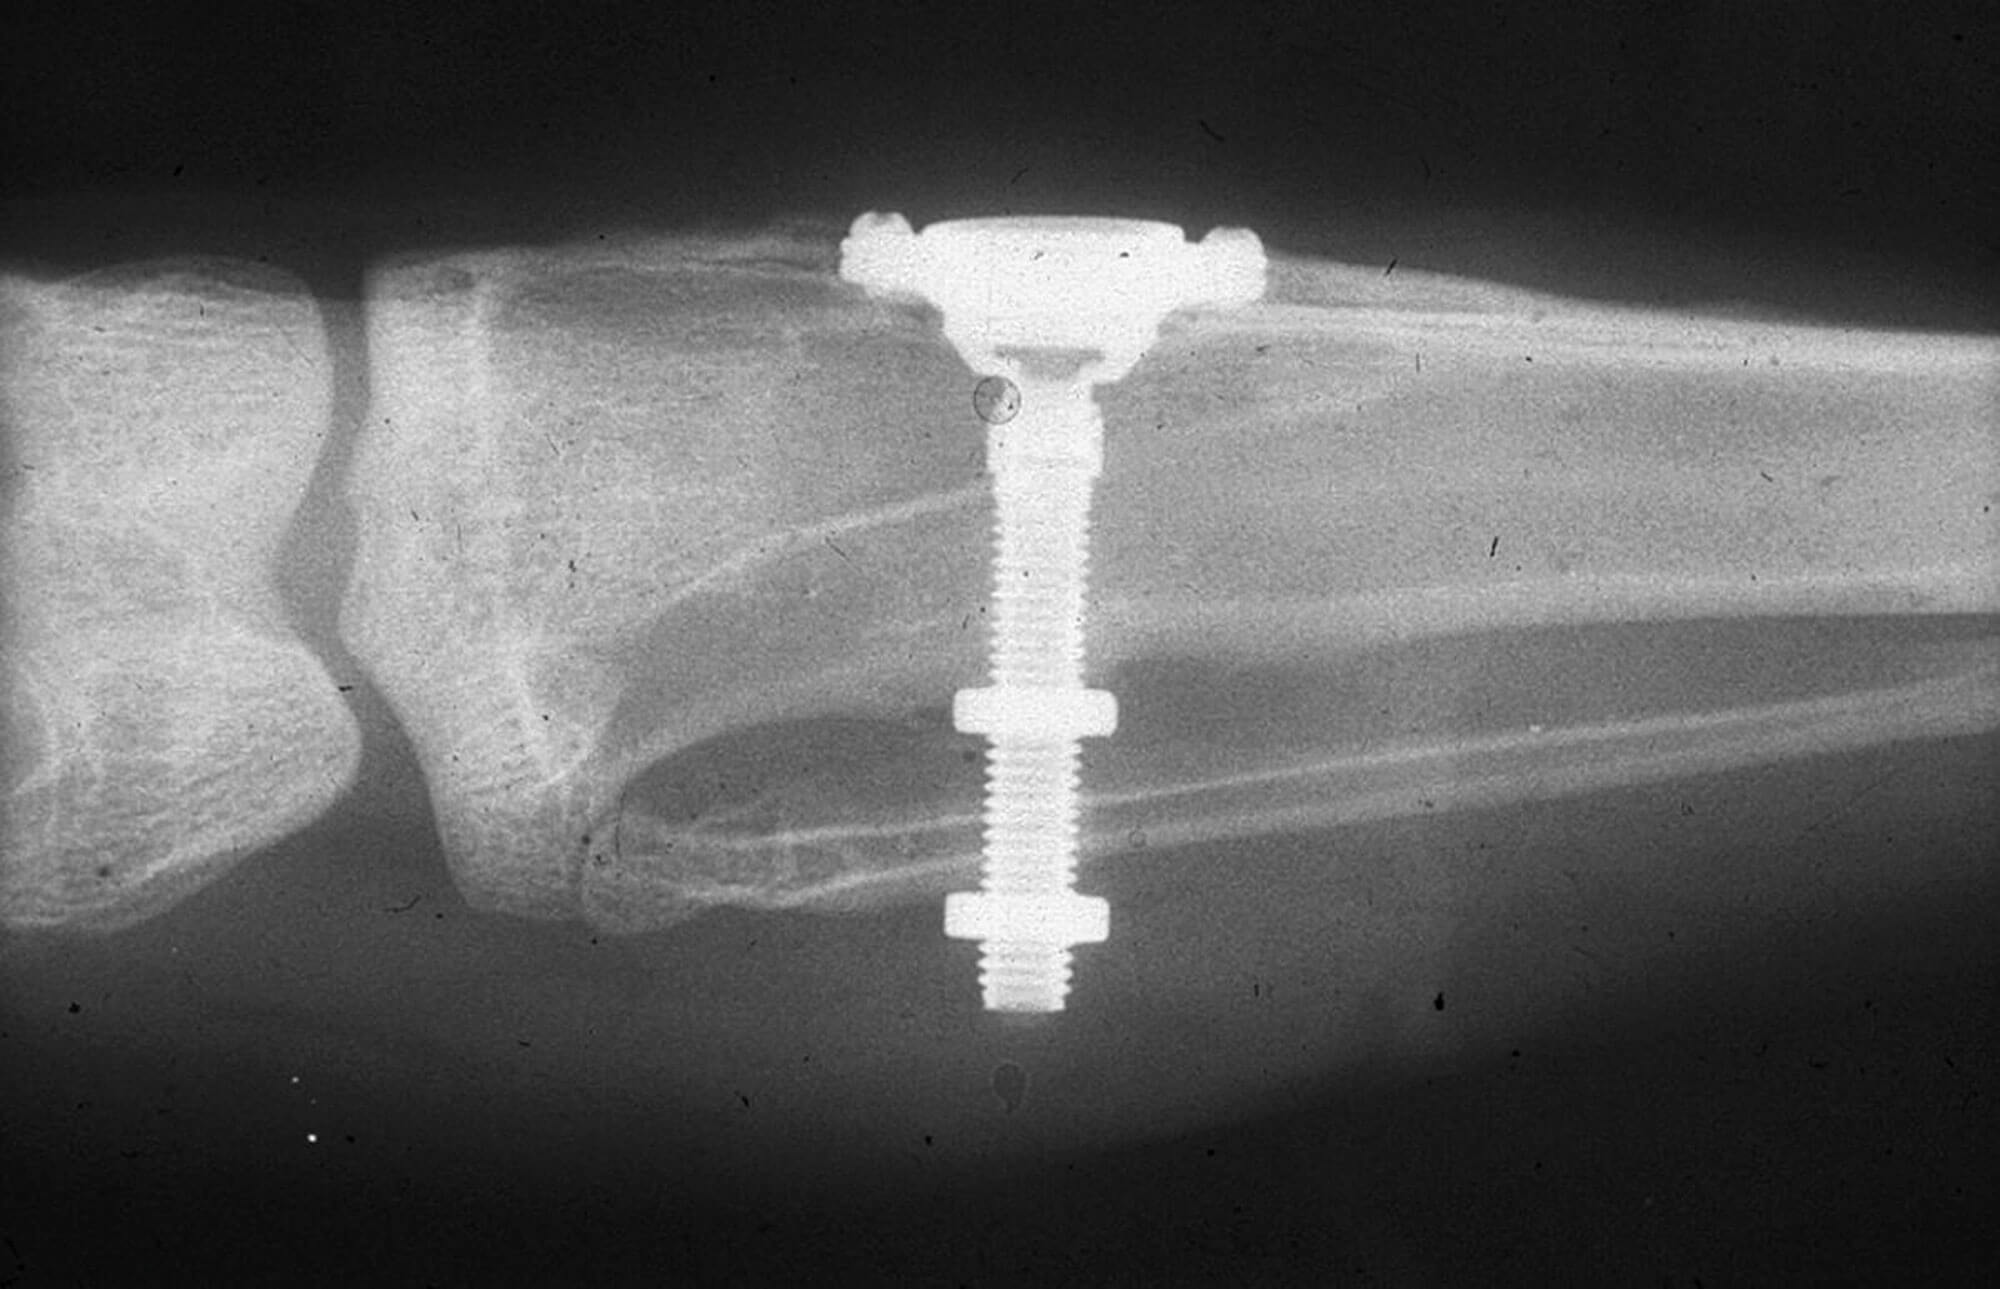

The x-ray from Brånemark’s original historic experiment on the rabbit’s leg. Image courtesy of Wikimedia Commons.